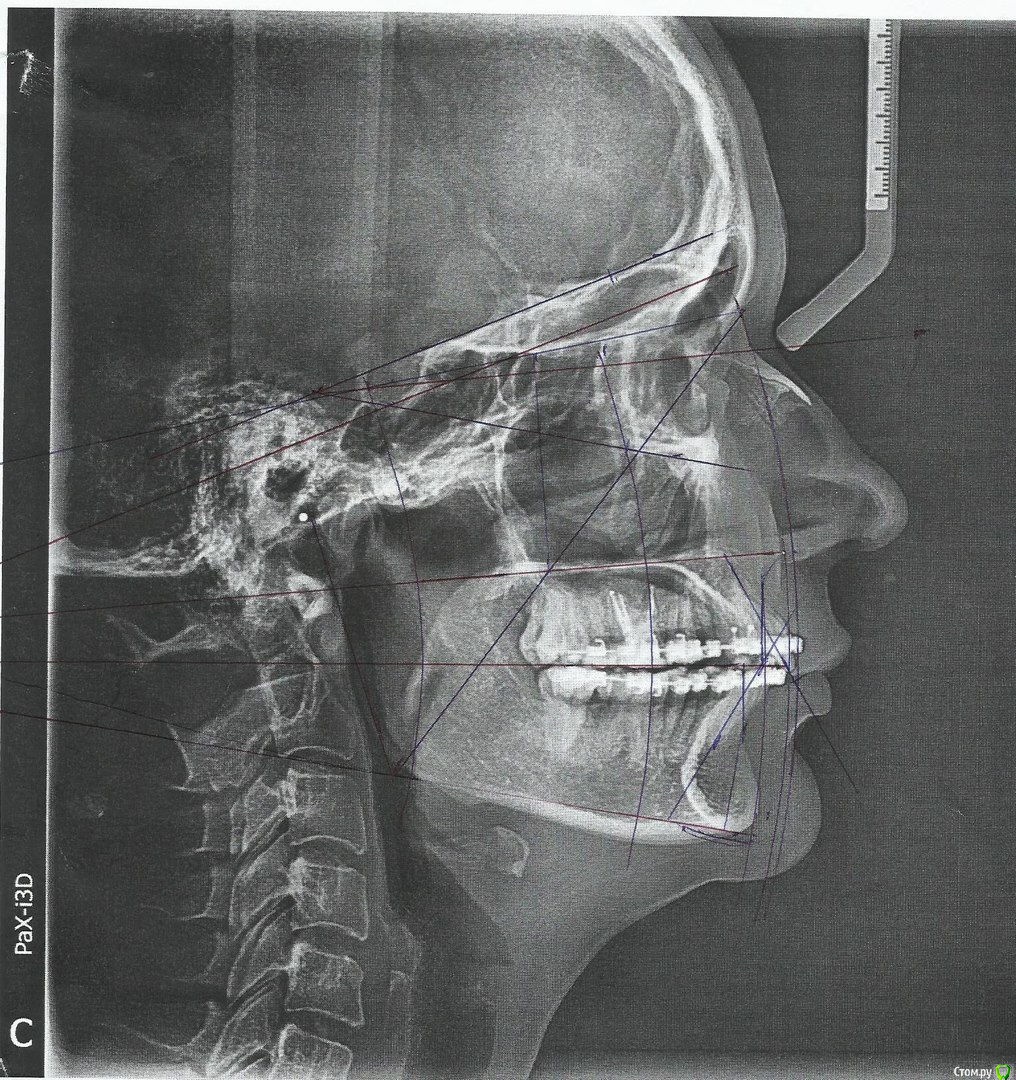

losenok83 Опубликовано 4 сентября, 2016 Автор Поделиться Опубликовано 4 сентября, 2016 Здравствуйте, очень нужна ваша помощь снова! Я обошла много ортодонтов в своем городе на предмет дальнейшего лечения. В конце концов мое самочувствие более менее менее улучшилось только после ортотика. В дальнейшем мне сказали ортодонт поставит мои зубы на такую высоту. Скажите пожалуйста это правда возможно, на такую высоту вытянуть свои верхние и нижние зубы? И еще изначально этот ортодонт планировала что в этом ортотике Н,Ч, выйдет вперед , а потом ее расширят. Поскольку этого не произошло, сказала что просто раздвинут место для раннее удаленных 4-рок на В,Ч. пружинами. А я очень боюсь, что в результате зубы будут торчать вперед как раньше.Разве нет? Расчет ТРГ на данный момент лечения. И вид челюстей в ортотике. Ссылка на комментарий

Yana guapa Опубликовано 6 сентября, 2016 Поделиться Опубликовано 6 сентября, 2016 1. где сам снимок трг? 2. вы из ростова но расчет я так понимаю делал московский врач а не ваш? 3. мне трудно комментировать данное лечение, потому что мой план лечения отличался бы ... но на мой взгляд - высота завышена, и явно далека от терапевтической нормы... Нужен снимок ТРГ а не расчеты чужие . (с удовольствием послушаю мнение коллег) 4. не первый раз вижу расчеты с такой фамилией, заинтересовала графа - "АНГУЛЯЦИЯ резцов вч и нч" - комментарий ПРОТРУЗИЯ. (это к коллегам вопрос) интересный расчет))) 2 Ссылка на комментарий

losenok83 Опубликовано 6 сентября, 2016 Автор Поделиться Опубликовано 6 сентября, 2016 Yana guapa , спасибо, что откликнулись! А как вы сами лечили бы такой случай ? Вот Ортодонт, которого вы рекомендовали мне весной. Говорила о постоянных керамических накладках на все жевательные зубы. А на 5-ки верхние поставить коронки, чтобы увеличить их ширину и тем самым заполнить промежутки оставшиеся. Мне этот вариант как-то не очень понравился. Жалко было столько здоровых зубов пилить! Ну а все остальные настаивали на прежнем плане лечение с закрытием промежутков. Расчеты делал московский врач, его сайт в интернете показался мне весьма интересным, а его расчеты более полные на мой дилетантский взгляд, он вроде ученик Савинова . В Ростове я поняла вообще мало кто заморачивается расчетами, как сказал мне мой первый ортодонт считающийся одним из лучших в городе, ТРГ нужно только, чтобы бы мягкие ткани посмотреть! Ссылка на комментарий

Maxfac Опубликовано 7 сентября, 2016 Поделиться Опубликовано 7 сентября, 2016 "АНГУЛЯЦИЯ резцов вч и нч" - комментарий ПРОТРУЗИЯ )) Ссылка на комментарий

Skip Опубликовано 7 сентября, 2016 Поделиться Опубликовано 7 сентября, 2016 4. не первый раз вижу расчеты с такой фамилией, заинтересовала графа - "АНГУЛЯЦИЯ резцов вч и нч" - комментарий ПРОТРУЗИЯ. (это к коллегам вопрос) интересный расчет))) Яна, а что именно вызывает у Вас смех и сарказм? Вы знакомы или работаете с анализом Sassouni Plus? 1 Ссылка на комментарий

Yana guapa Опубликовано 7 сентября, 2016 Поделиться Опубликовано 7 сентября, 2016 Яна, а что именно вызывает у Вас смех и сарказм? Вы знакомы или работаете с анализом Sassouni Plus? Алексей Олегович, зачем такая путаница?? существует определение - ангуляции и инклинации. и если в Sassouni плюс "ангуляция" нечто иное чем традиционно принято считать , то зачем все это? я не писала что врач не прав, я написала - интересный расчет!)) Ссылка на комментарий

Skip Опубликовано 7 сентября, 2016 Поделиться Опубликовано 7 сентября, 2016 Алексей Олегович, зачем такая путаница?? существует определение - ангуляции и инклинации. и если в Sassouni плюс "ангуляция" нечто иное чем традиционно принято считать , то зачем все это? я не писала что врач не прав, я написала - интересный расчет!)) А в чём всё-таки путаница? Мне знаком один единственный перевод с англ. слова angulation, а именно - образование угла; расположение под углом ( Англо-Русский Медицинский Словарь, Акжигитов Г.Н. Бенюмович М.С. Чикорин А.К. 1992 г.) Может я уже стал стар и отстал от жизни...))) Ссылка на комментарий

Yana guapa Опубликовано 7 сентября, 2016 Поделиться Опубликовано 7 сентября, 2016 А в чём всё-таки путаница? Мне знаком один единственный перевод с англ. слова angulation, а именно - образование угла; расположение под углом ( Англо-Русский Медицинский Словарь, Акжигитов Г.Н. Бенюмович М.С. Чикорин А.К. 1992 г.) Может я уже стал стар и отстал от жизни...))) ну что Вы, Алексей Олегович , на себя наговариваете!)) Вы бодры и веселы))) это я видимо слишком зеленая!)) меня учили что ангуляция может быть положительной или отрицательной в вертикальной плоскости (соответственно коронковая или корневая), но вот понятие "протрузия" все-таки применяли для измерения угла наклона зуба в сагитальной плоскости Ссылка на комментарий

Skip Опубликовано 7 сентября, 2016 Поделиться Опубликовано 7 сентября, 2016 ну что Вы, Алексей Олегович , на себя наговариваете!)) Вы бодры и веселы))) это я видимо слишком зеленая!)) меня учили что ангуляция может быть положительной или отрицательной в вертикальной плоскости (соответственно коронковая или корневая), но вот понятие "протрузия" все-таки применяли для измерения угла наклона зуба в сагитальной плоскости Вас учили адепты техники прямой дуги и там действительно то, о чём Вы пишите. А у адептов всегда - шаг вправо шаг влево расстрел)) У нас всё проще, как собственно и в английском языке) Если, к примеру, Вы закажете для себя провести анализ ТРГ Sassouni, где-нибудь в районе западного Бруклина штата Нью-Йорк, то Вам пришлют вот такой формуляр с отчётом, где в слово АНГУЛЯЦИЯ, как можно убедиться, вкладывается несколько иной смысл: http://i6.pixs.ru/storage/5/1/1/SassouniPl_8251589_23209511.png Ссылка на комментарий